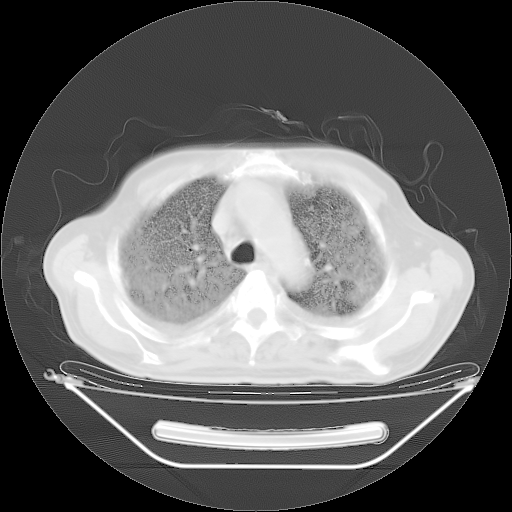

胸腹部CT,诊断意见:左上肺叶钙化灶、左侧胸膜局限性增厚并钙化、胆囊炎。描述部分肺组织呈磨玻璃样改变。